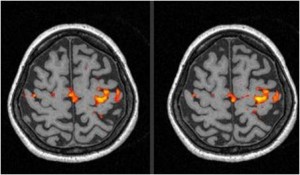

Il team di ricercatori della QMRI Tech è esperto di studi di neuroimaging mediante tecniche RM di Perfusione con mezzo di contrasto (DSC e DCE MRI), Diffusione (DWI e DTI), IVIM, Spettroscopia, fMRI Bold, Rilassometria, Texture Analysis.